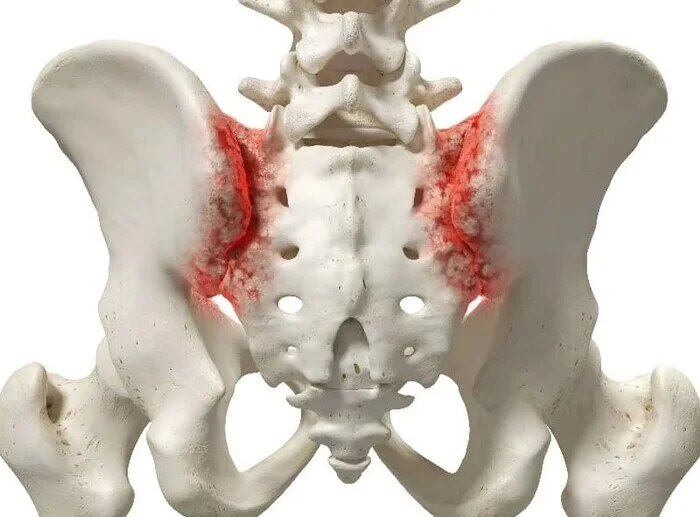

Сакроилиит — это воспаление одного или обоих крестцово-подвздошных суставов. Рентгенограммы поясничного отдела позвоночника пациента с длительным, выраженным болевым синдромом(6 мес.) в пояснице, с временным эффектом от приема НПВС. При описании снимков выраженной костной патологии в поясничном отделе позвоночника не выявлено: структура тел позвонков не изменена, травматических, деструктивных изменений не выявлено, субхондральный склероз замыкательных пластин тел позвонков отсутствует, краевые остеофиты тел позвонков не выявлены, имеется не выраженное неравномерное сужение межпозвонковых щелей как начальное проявления остеохондроза-такая рентгенологическая картина не дает столь выраженного и длительного болевого синдрома. Обращают на себя внимание крестцово-подвздошные сочленения(КПС),отмечается неравномерное не выраженное сужение щелей КПС с локальными участками расширения, субхондральный склероз- более выраженный слева, имеются двусторонние краевые остеофиты, в нижней трети левого К

Рентгенограммы поясничного отдела позвоночника пациента с длительным, выраженным болевым синдромом(6 мес.) в пояснице, с временным эффектом от приема НПВС. При описании снимков выраженной костной патологии в поясничном отделе позвоночника не выявлено: структура тел позвонков не изменена, травматических, деструктивных изменений не выявлено, субхондральный склероз замыкательных пластин тел позвонков отсутствует, краевые остеофиты тел позвонков не выявлены, имеется не выраженное неравномерное сужение межпозвонковых щелей как начальное проявления остеохондроза-такая рентгенологическая картина не дает столь выраженного и длительного болевого синдрома.

Обращают на себя внимание крестцово-подвздошные сочленения(КПС),отмечается неравномерное не выраженное сужение щелей КПС с локальными участками расширения, субхондральный склероз- более выраженный слева, имеются двусторонние краевые остеофиты, в нижней трети левого КПС суставная щель не ровная, "изъеденная", по причине наличия единичных эрозий костной ткани. Заключение: Двусторонний сакроилиит 2 ст.(более выраженный слева).

Рентгенологические градации сакроилиита в соответствии с модифицированными Нью-Йоркскими критериями диагноза англизирующего спондилита:

• 0 стадия - Отсутствие изменений

• 1 стадия - Подозрение на наличие изменений (отсутствие конкретных изменений, смазанность субхондрального слоя).

• 2 стадия - Минимальные изменения (небольшие локальные области с эрозиями или склерозом, сужение или неравномерность суставной щели.)

• 3 стадия - Безусловные изменения (умеренный или значительный сакроилиит с эрозиями, склерозом, расширением, сужением щели или частичным анкилозом)

• 4 стадия - Далеко зашедшие изменения (полный анкилоз)